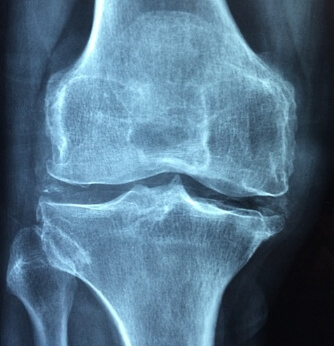

그럼, 관절염을 예방하기 위해서 먼저 관절염의 다양한 원인에 대해서 알아볼 필요가 있겠습니다. 관절염은 하나 이상의 관절사이에 염증이 발생하여 통증과 움직이는 기능이 어려워지는 것을 일반적으로 이야기합니다.

1. 관절 통증관절염의 초기에 나타나기 시작해서 가장 대표적인 증상입니다. 신체의 관절 부위 주변에 작은 불편감을 갑자기 느끼게 되거나 통증을 경험하게 됩니다. 그리고 이러한 관절의 통증은 시간이 경과함에 따라서 나중에는 더욱 극심한 통증으로 나타나며, 통증이 계속될 수도 있고 부정기적으로 나타났다가 사라지기를 반복할 수도 있습니다.

2. 경직성 특히 아침과 같이 활동을 하지 않다가 관절을 움직이면 이유 없이 뻣뻣해짐을 느끼는 것은 대표적인 관절염의 초기 증상으로 요즘과 같은 날씨가 추운 겨울철에 많이 느낄 수 있습니다. 그러나, 초기에는 이러한 강직성에도 불구하고 천천히 자연스러운 움직임을 계속 주게 되면 활동성이 개선되는 경향이 있습니다.

3. 운동능력 감소위 경직성과 연계되는 증상으로 관절염은 신체의 유연성과 운동능력에 영향을 주게 되는데 초기에는 관절은 완전히 구부리는 동작이나 곧게 펴는 동작을 할 때 어려움을 겪을 수 있습니다.

4. 부종관절염이 일부 증상으로 해당하는 관절 부위에 부종이 나타납니다. 해당 부위는 평상시 보다 붓거나 손으로 만졌을 때 따듯함을 느낄 수도 있고 발적 증상을 보이기도 합니다.